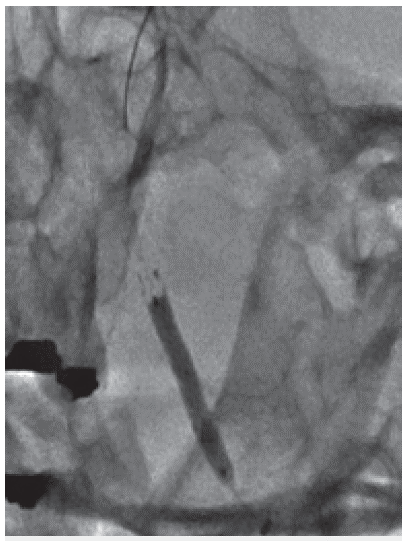

Reconstrucción arterial final de todo el segmento estenótico

Figura 4: Reconstrucción arterial final de todo el segmento estenótico